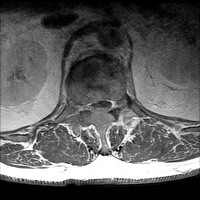

MRI: Sag T1 FS Post L-spine can be paired with Ax T1 FS Post T12 lesion

Sagittal T1 fat saturated post-contrast images of the lumbar spine and axial T1 fat saturated post-contrast images through the T12 lesion demonstrate diffusely abnormal signal throughout the visualized marrow, with areas of patchy enhancement corresponding to active myelomatous lesions.  There is extensive spinous process involvement at the T12 level with epidural extension, resulting in severe central spinal canal stenosis and complete effacement of CSF signal in the thecal sac. Mild to moderate compression deformity of T12.